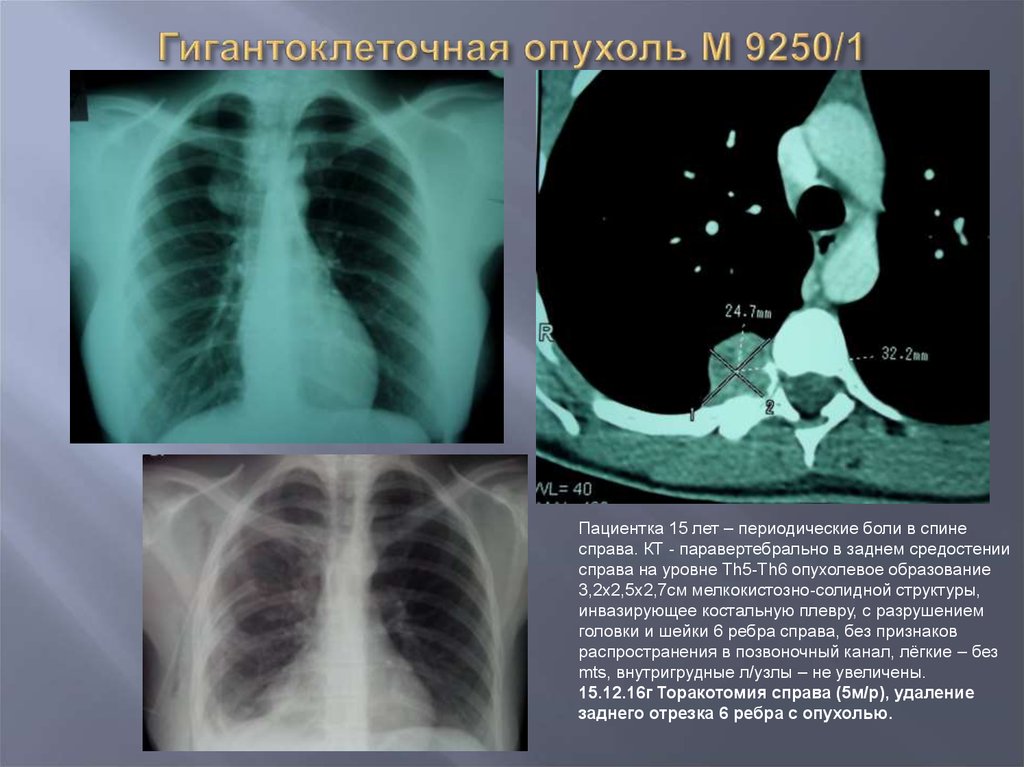

Рентгеновские снимки опухоли Панкоста